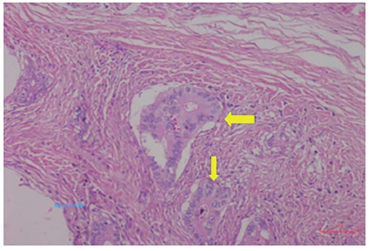

Flecha: trombos tumorales linfáticos

Figura 6. Patrón infiltrante con formación de figuras (back to back), cribas y ausencia de estroma fibrovascular entre las glándulas neoplásicas. Hematoxilina y eosina, 100X.

Fuente: Servicio de Patología, Hospital Irma Lourdes Tzanetato.